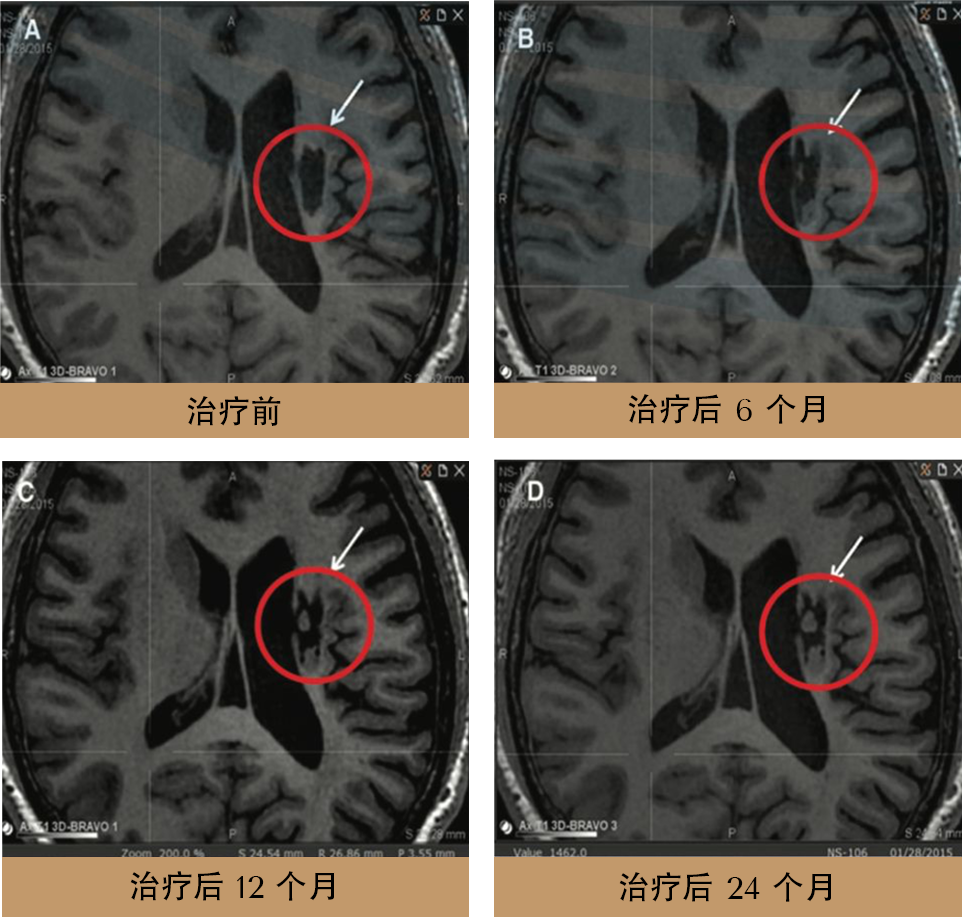

真实经历.真实改变